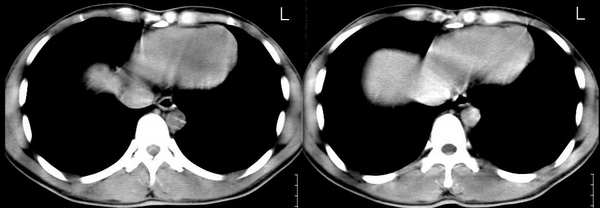

男,21岁,一年前确诊肺结核(未见年前照片),经抗结核治疗出院。2005年9月26日照片与2006年3月1日照片对比,病变反而增多,但病人症状不明显.疑惑?

ct扫描: